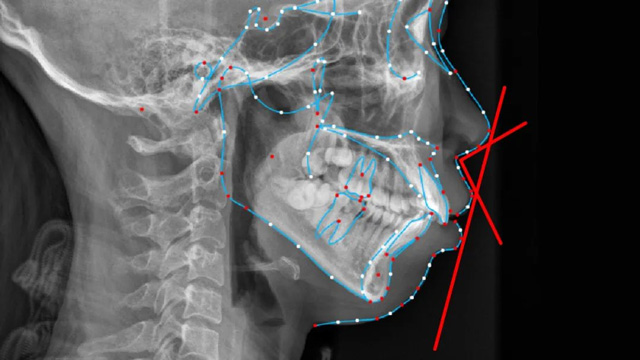

我们通过正畸治疗把下颌导出,恢复到正常的面型比例和上下颌的对应关系,就可以很好地改善以上情况。网友关注的这位女孩的情况是一个II类错颌畸形,同时是高角面型,错颌畸形是一种口腔疾病,确实需要治疗。

儿童下巴后缩治疗前后